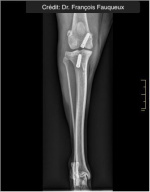

Radiologické snímky